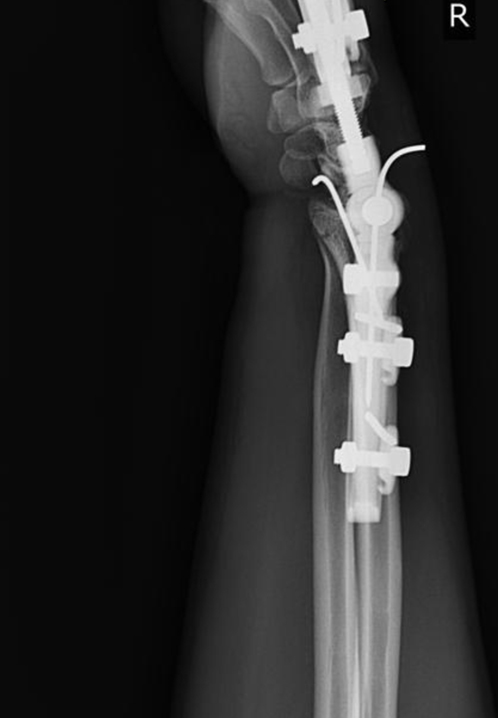

Dynamic Distal Radius

External Fixators

Concept

Distal radius fractures represent the most prevalent fracture type encountered in emergency settings. External fixation stands out as one of the optimal treatment modalities for managing distal radius fractures, particularly beneficial in cases involving articular or metaphyseal comminution.

Adjustment of the articular components of the external fixator is conducted in accordance with radiological parameters of the unaffected side.